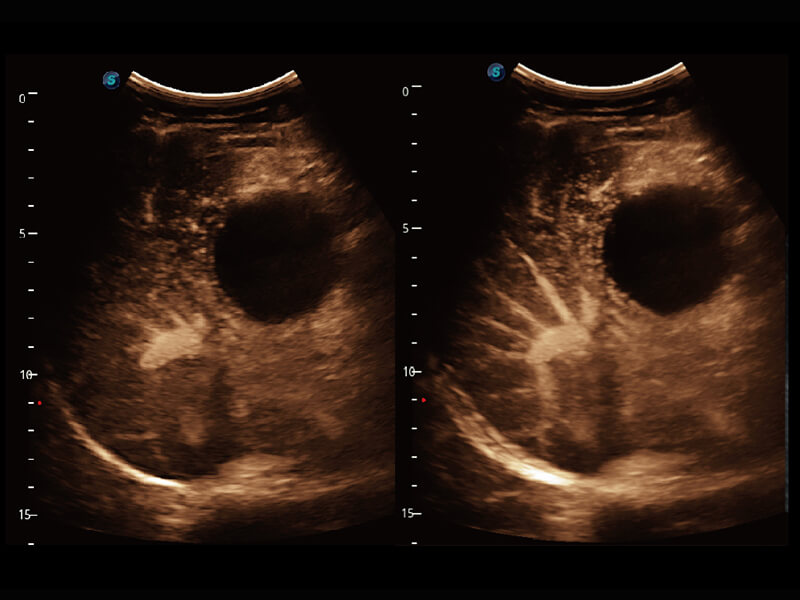

前端信号 真知灼见

S60探头工艺,从前端信号处理每一个环节采集无损声学数据,真实还原组织原貌,再现解剖细节。

• 腹部单晶体探头( C1-6A )

• 新型复合材料探头( 12L-A )

• 高分辨率容积探头( VC2-9A )